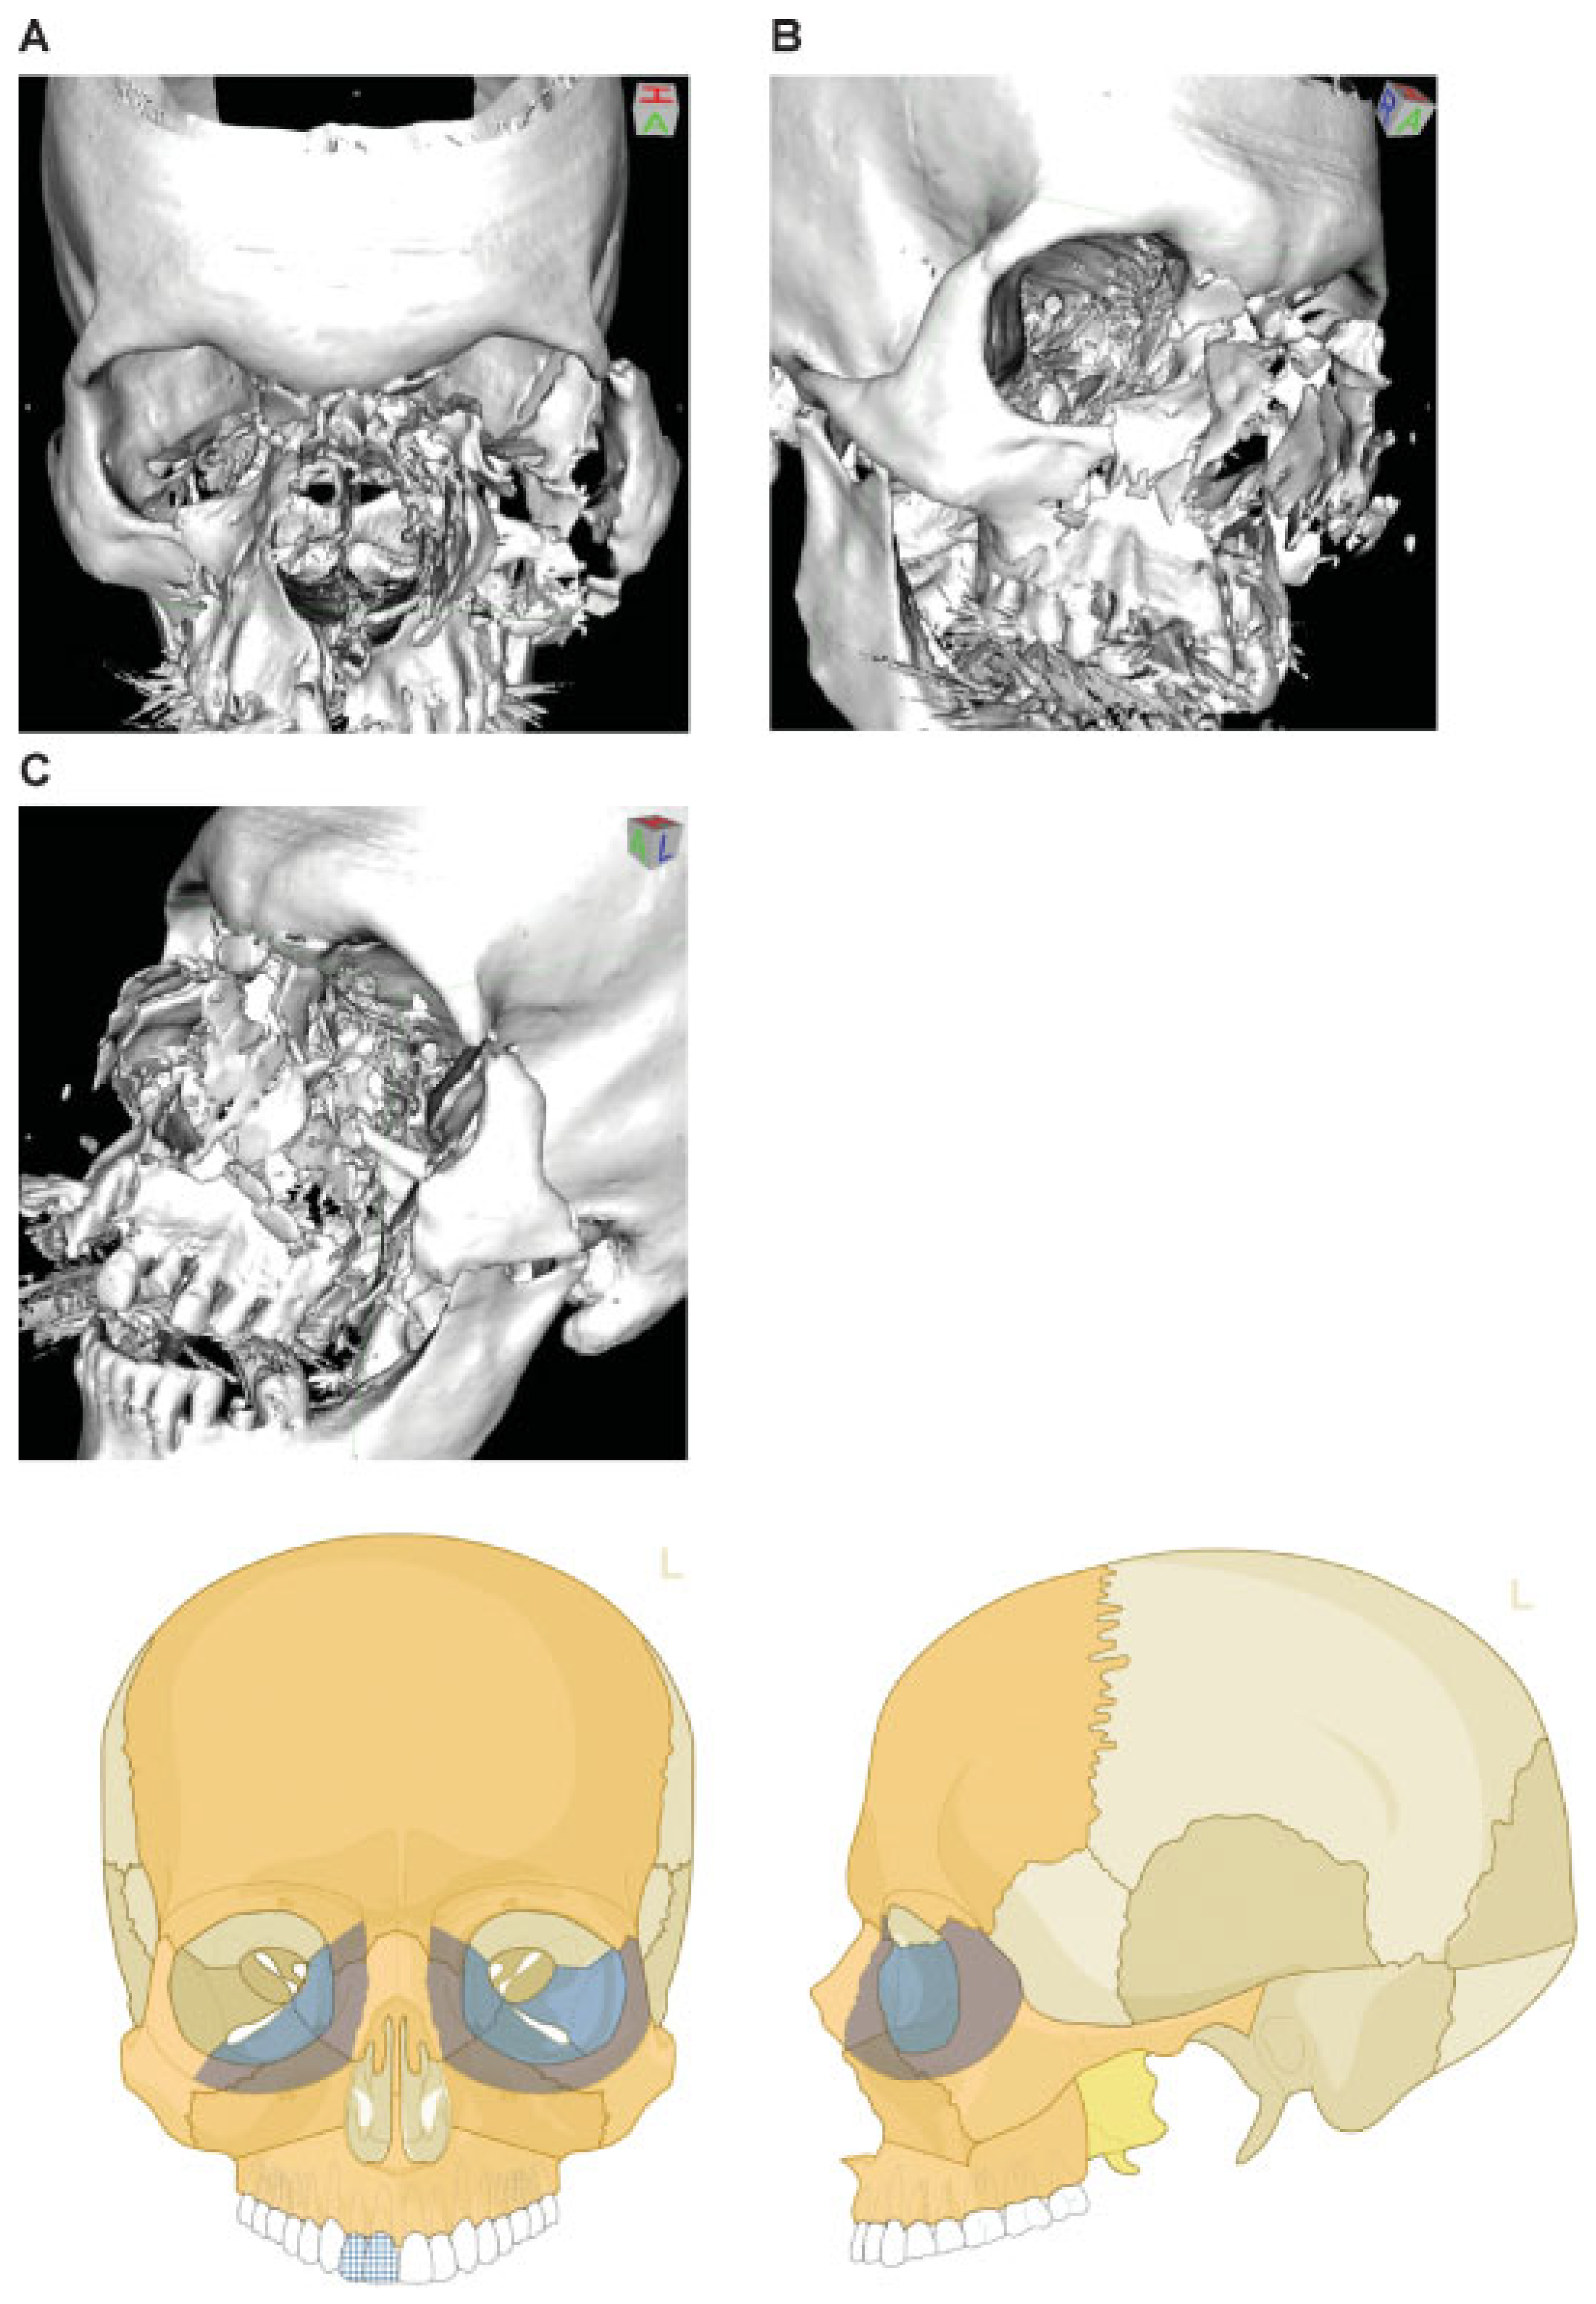

Figure 9.

Naso-orbito-ethmoidal fracture (Example 2)—NOE extreme Type III bilateral. Imaging: Three-dimensional (3D) computed tomographic scans (A) frontal view, (B) oblique lateral view right, and (C) oblique lateral view left. Narrative description: Medium-/small-sized fragments and extreme displacement (loss of interfragmentary contact) in a bilateral Naso Orbito Ethmoid Fracture in combination with a Le Fort I, II fracture, and left zyogma fracture. (D) Level 3 Code: 92 Z1i.I1i.L1.Pt0.Oim.U1m.Omil.Pt0.L1.I1i.Z1li - 93 m.M - 94 F1.m.F1m, Orbit (right): R(im).W1(im)2(im), Orbit (left): R(lim).W1(lim)2(lim). This case example CMTR-92-105 is made available electronically for viewing using the AOCOIAC software at www.aocmf.org/classification. Note: Involvement of midface and craniofacial transition as a consequence of fractures extending into the superomedial quadrants of the orbital rim - this is indicated by the marking of the entire frontal bone area.